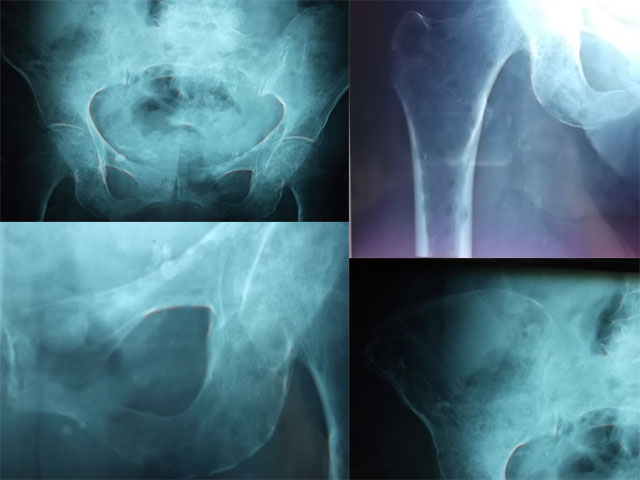

Atteintes osseuses caricaturales d’un myélome multiple chez une octogénaire

Une patiente âgée de 87 ans, hypertendue depuis 30 ans, était admise pou bilan étiologique de douleurs osseuses au niveau du bassin, résistantes aux antalgiques usuels évoluant depuis 4 mois avant son admission dans un contexte d'altération de l'état général. Au bilan biologique, elle avait une anémie normochromenormocytaire (Hb : 8,5 g/dL, VGM : 86,1 µ3), une créatinine à 103 µmol/l avec une clairance à 22 ml/mn, une VS à 93 mm, une hyper gammaglobulinémie d'allure monoclonale à 31,45 g/L. la calcémie était normale à 2,5 mmol/L. Le bilan radiologique des os douloureux a révélés de multiples géodes à l'emporte pièce au niveau du bassin surtout au niveau des ailes ischio-pubiennes et du tiers supérieur du fémur et une fracture tassement au niveau de la 12ème vertèbre thoracique. La ponction sternale a montré une infiltration médullaire estimée à au moins 40% par une population plasmocytaire franchement dystrophique. L'immunoélectrophorèse des protéines sérique a objectivé la présence d'une immunoglobuline monoclonale de type IgG Kappa. La recherche de protéinurie de Bence-Jones était négative. Le diagnostic de myélome multiple stade III A a été alors retenu. Vu l'importante atteinte osseuse, une prévention des chutes s'impose chez cette patiente à fin de réduire le risque de fractures.